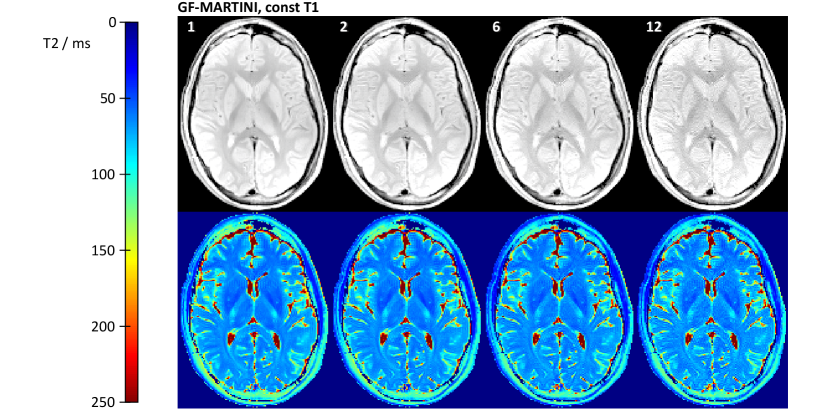

The mean T2 values obtained by GF-MARTINI are in remarkably good agreement with the fully sampled reference and very stable for all undersampling factors. Moreover, Fig. 7

Refer to caption

Figure 7: Spin-density and color-coded T2 maps of the human brain obtained by GF-MARTINI reconstructions with validity mask and constant T1 = 1000 ms for undersampling factors of 1, 2, 6 and 12. The corresponding measurement times were 12:54, 6:27, 2:09, and 1:05 min.

depicts reconstructions of the same data with the assumption of a constant T1 =1000 msabsenttimes1000ms=$1000\text{\,}\mathrm{m}\mathrm{s}$ for all pixels. It turns out that the GF-MARTINI reconstructions with constant T1 are almost indistinguishable from the results obtained with a full T1 map. The ROI analysis in Table III confirms this observation as all measurable deviations between the two GF-MARTINI versions remain within ± 1 msplus-or-minus 1 ms\pm\mbox{ }$1\text{\,}\mathrm{m}\mathrm{s}$.